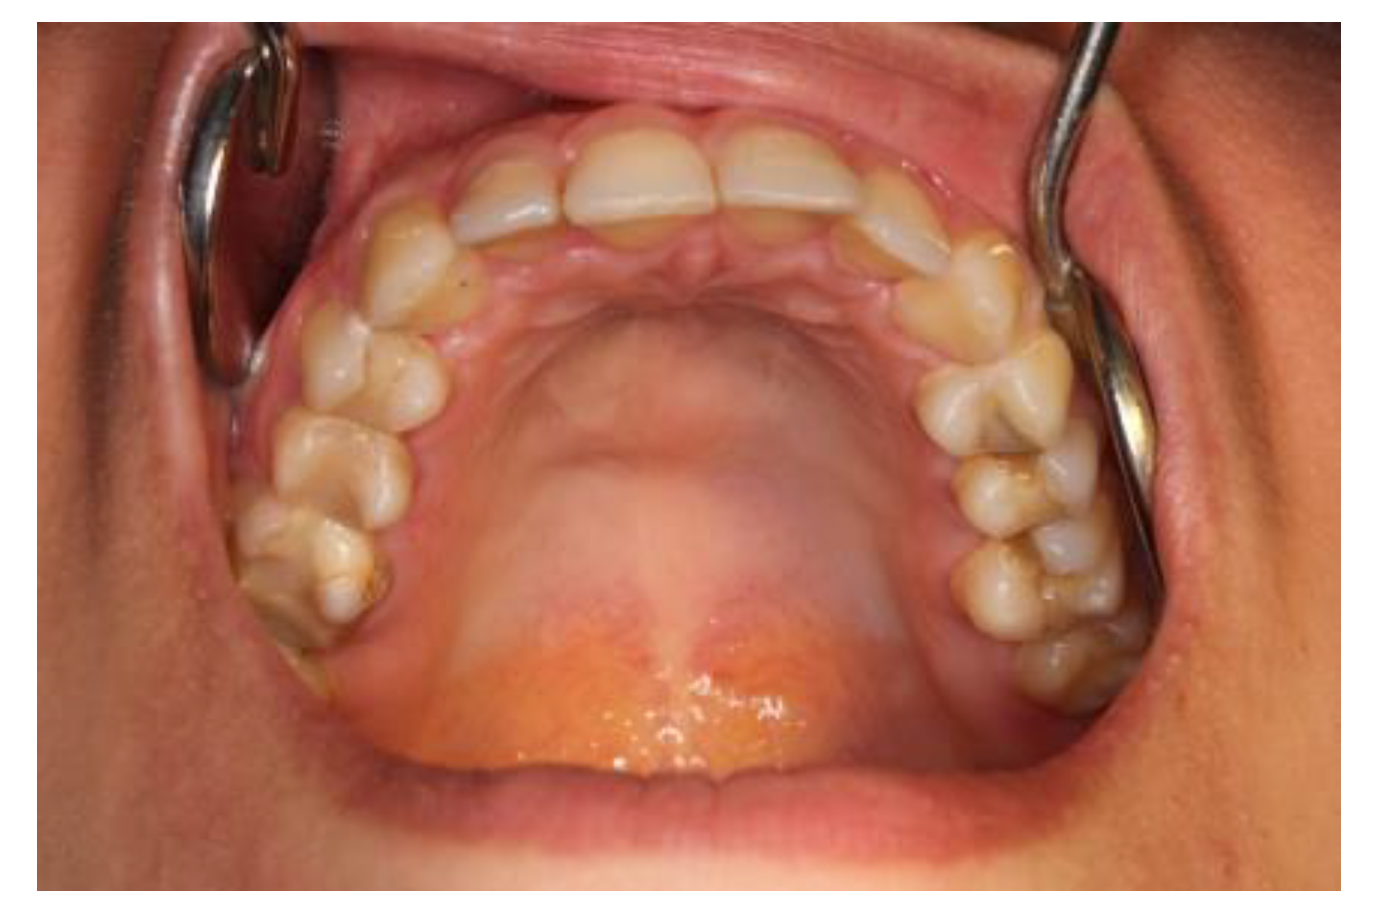

2.3. Case #3

| Case #3 | 18 y.o. | Female | Dexamethasone for 3 months—84 mg/21 mL at 2-day intervals | Mandible | Yes | Surgical treatment was necessary | 5 years |